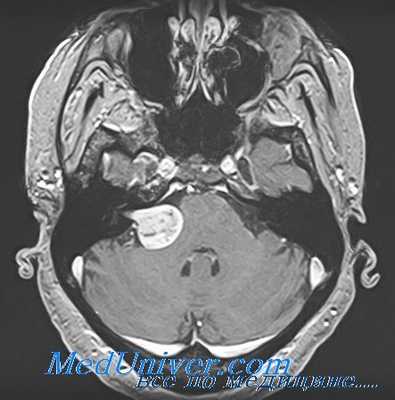

Диагноз выставляется на основании внешнего и неврологического осмотра, данных анамнеза. Во время проведения беседы на первом приеме врач просит больного описать характер головокружений. Для подтверждения диагноза проводится ряд инструментальных исследований:

- МРТ или КТ для оценки состояния дисков, кровеносных сосудов, нервных стволов, мягких тканей;